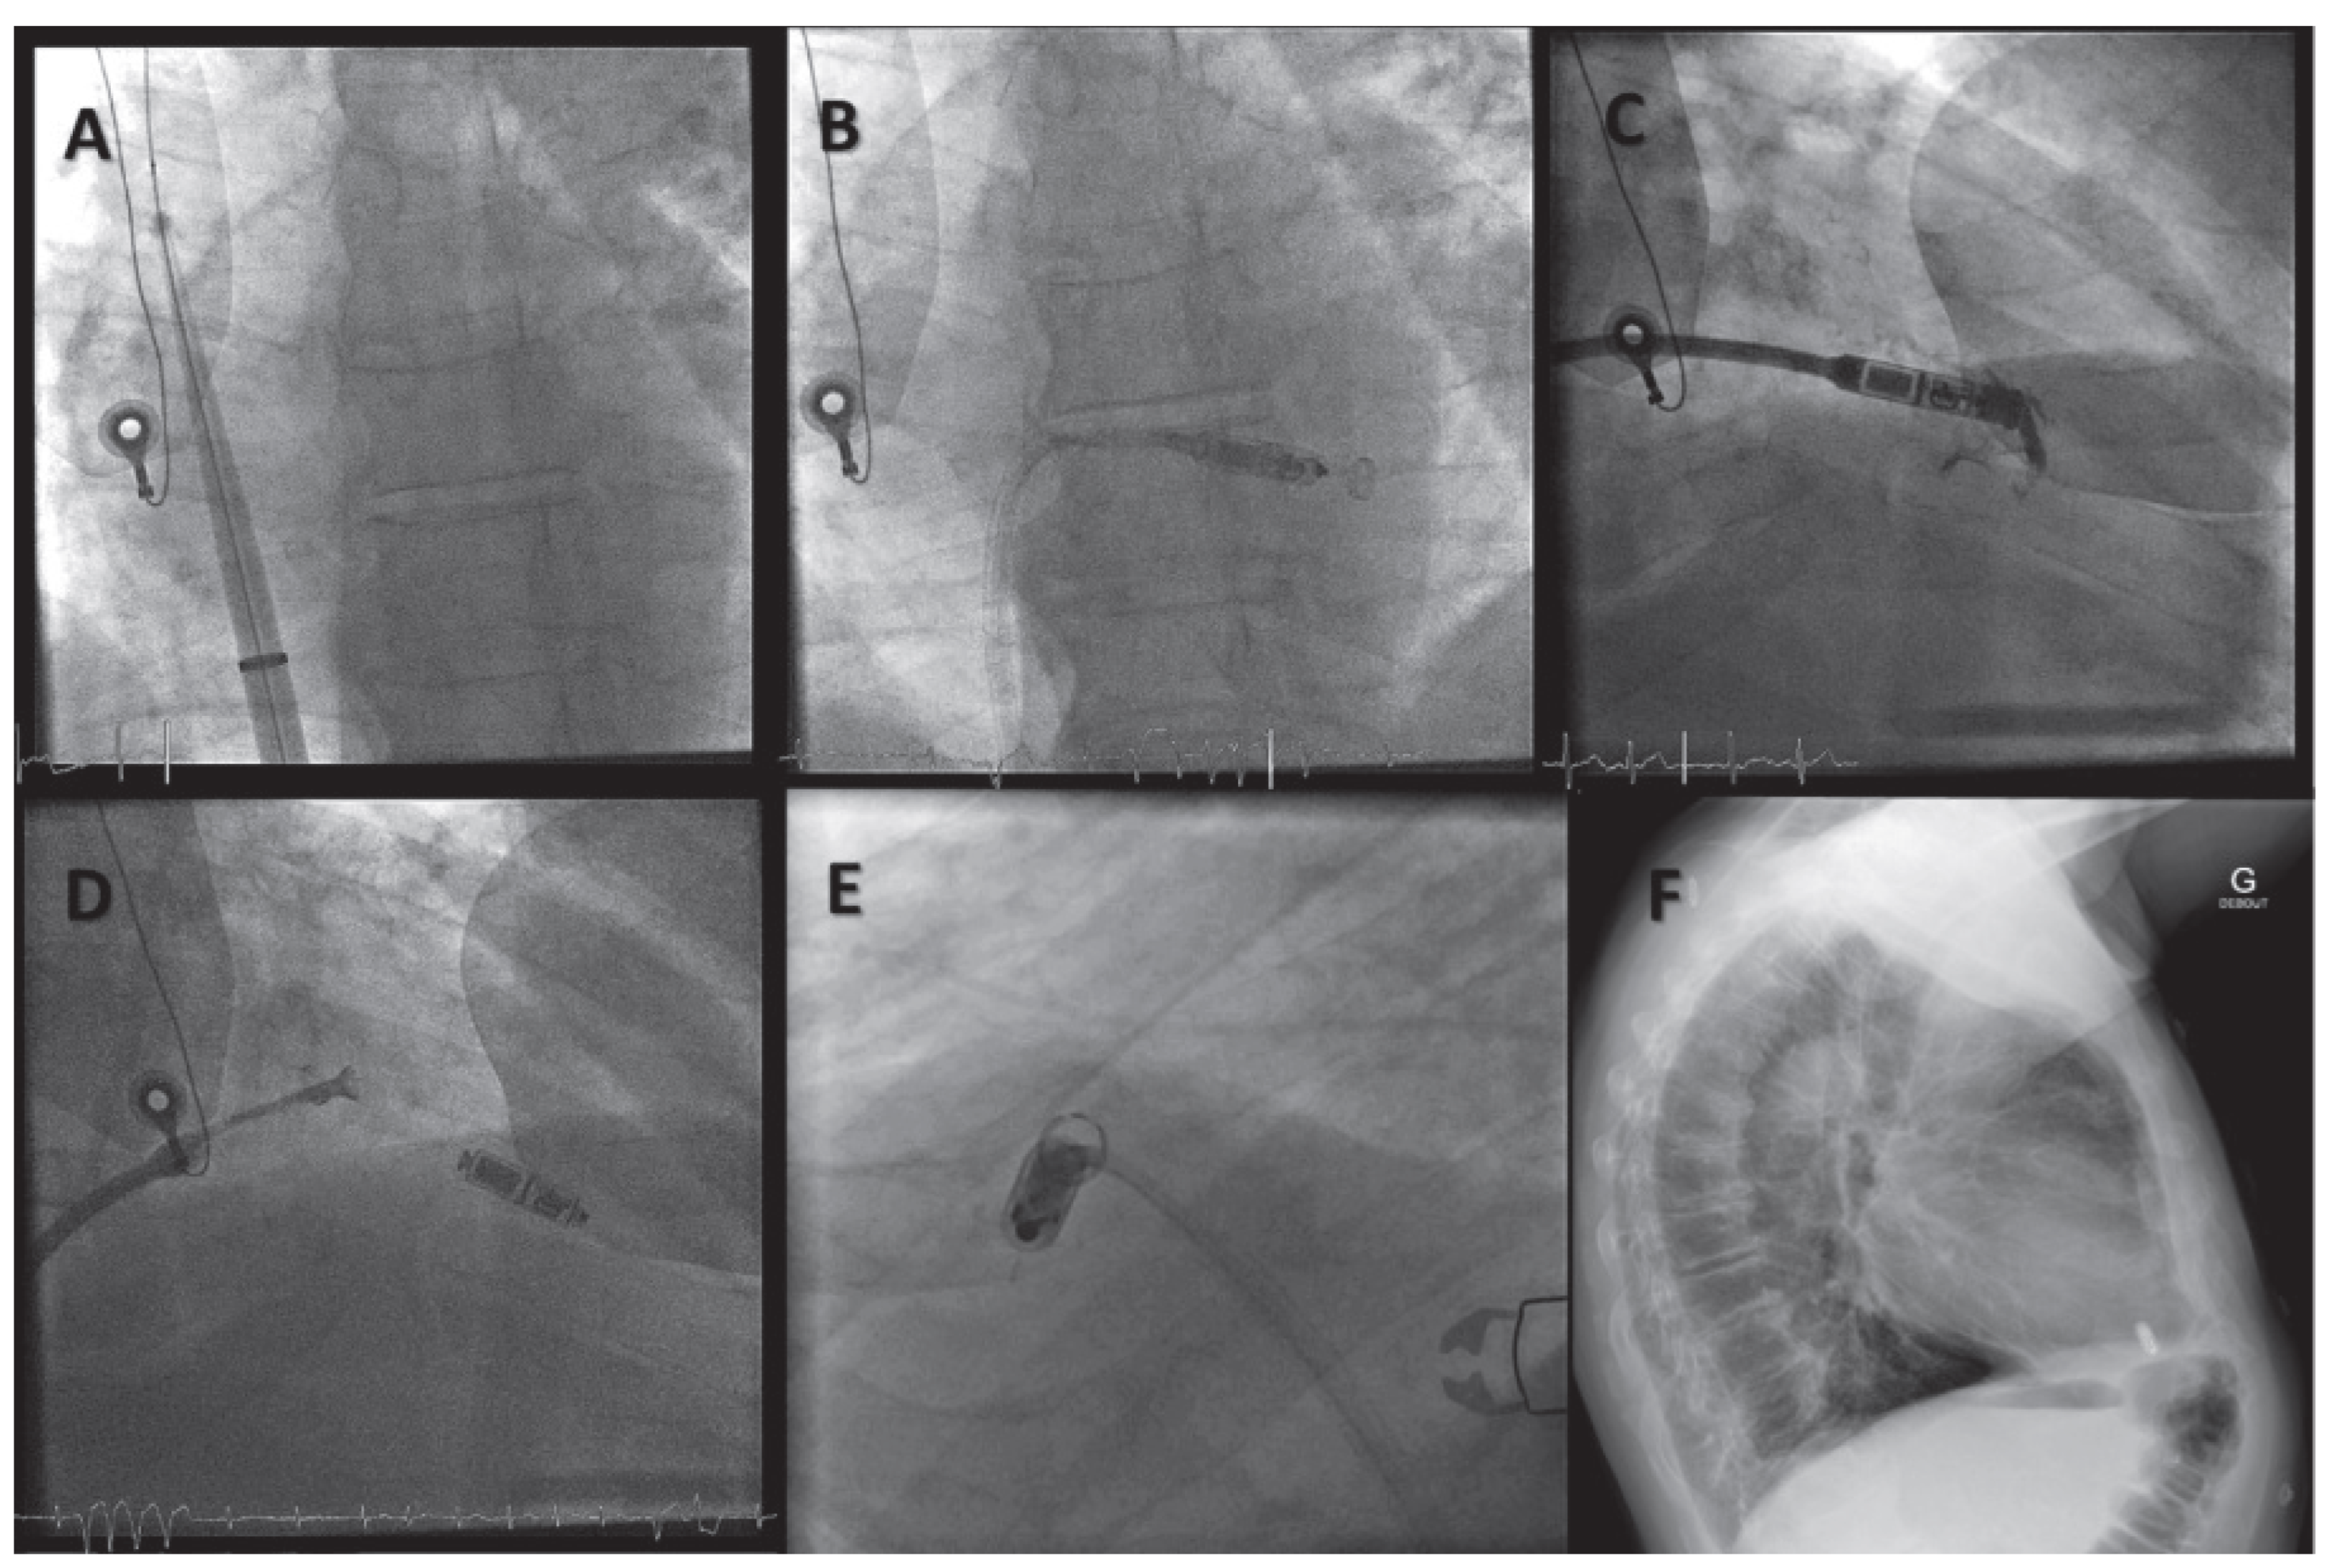

Wireless Cardiac Resynchronisation Therapy System